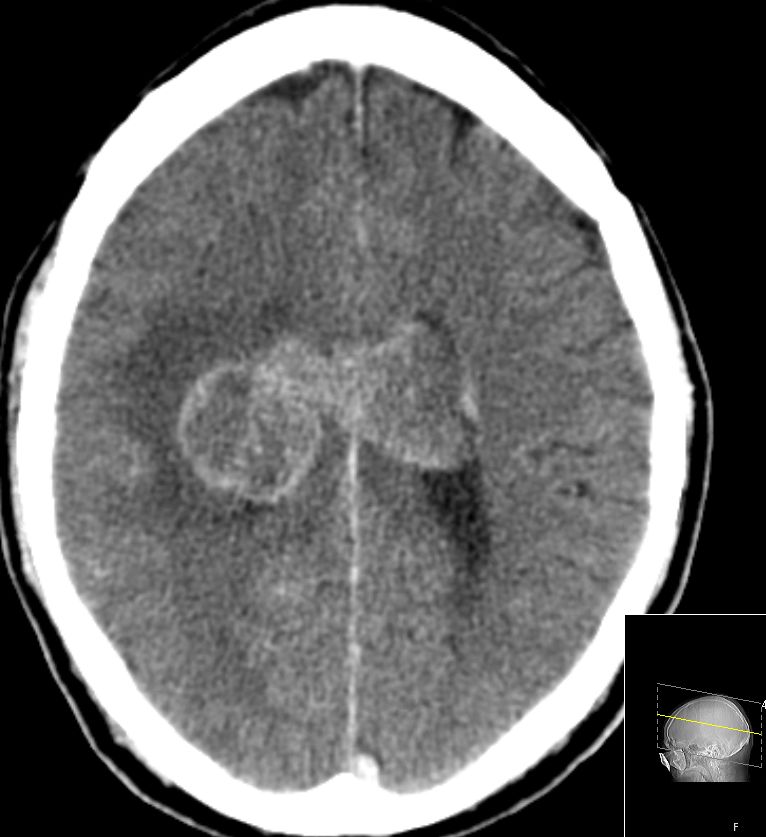

| zentrale Metastasen | 60-jähriger Mann, den vor einem Jahr ein

Plattenepithelkarzinom des linken Unterlappend cT2 pN2 Mo hatte. Nach 4x

Cisplatin-Vinorelbin und Bestrahlung vor 2 Monaten CR. Sturzes in der

Häuslichkeit eingewiesen werden. Jetzt Schwindel und zunehmende

Gangunsicherheit.

![]() |